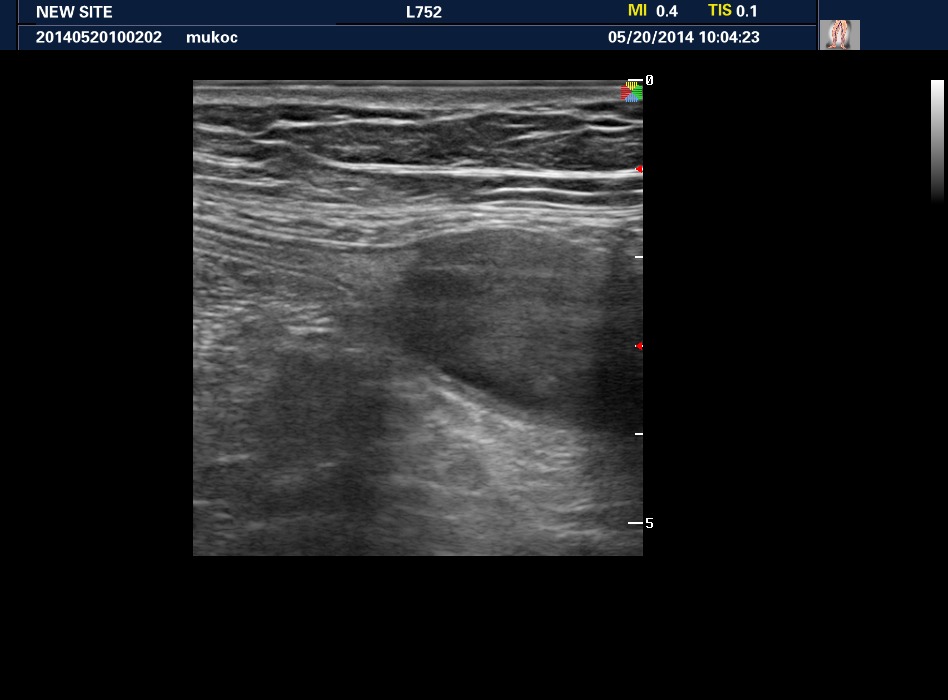

Мукоцеле аппендикса

Пожилая женщина. Дистальный участок аппендикса кистозно расширен, с жидким содержимым.

Не уверен, что случай удастся верифицировать, поэтому публикую его в "Консультациях"